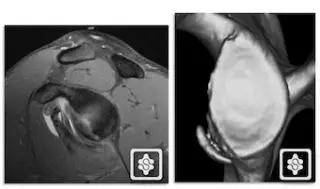

1. Hill-Sachs 损伤和反 Hill-Sachs 损伤

肩关节脱位时,肱骨头和关节盂发生撞击,肱骨头表面凹陷性骨折。

肩关节前脱位时发生的肱骨头后外侧凹陷性骨折,是经典的 Hill-Sachs 损伤(Hill-Sachs lesion);

-

而肩关节后脱位时发生的肱骨头前内侧凹陷性骨折,是反 Hill-Sachs 损伤(Reverse Hill-Sachs lesion/ McLaughlin lesion)。

Hill-Sachs 损伤的 MR 片(来源:Hill-Sachs Injuries of the Shoulder)

MRI 示反 Hill-Sachs 损伤程度 (来源:Anatomical Reconstruction of Reverse Hill-Sachs Lesions Using the Underpinning Technique. Orthopedics May 2012 - Volume 35 · Issue 5: e752-e757)